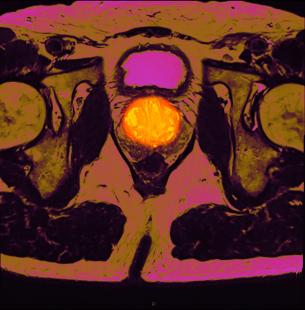

Aujourd’hui, il est possible de faire des biopsies ciblées par IRM multiparamétrique aux patients à risque de cancer de la prostate (sur la clinique et le PSA). « L’IRM multiparamétrique améliore la détection de cancers potentiellement agressifs (Gleason ≥ 7), caractérise les foyers tumoraux et précise les cibles à biopsier », indique le spécialiste. Dans l’essai PROMIS (1), elle a démontré sa capacité à limiter à 25 % les biopsies inutiles.

Pour détruire la tumeur au stade précoce en laissant le reste de la glande intacte, des techniques mini-invasives apparaissent, en cours d’évaluation. Ces innovations thérapeutiques sont intimement liées aux progrès de l’imagerie et de la fusion. La tumeur est repérée en IRM, puis les images sont transposées par logiciel sur l’échographe pour repérer et traiter électivement la tumeur. « Les résultats sont préliminaires. Un recul d’au moins 5 ans est nécessaire pour connaître leur pertinence », note le Pr Peyromaure.